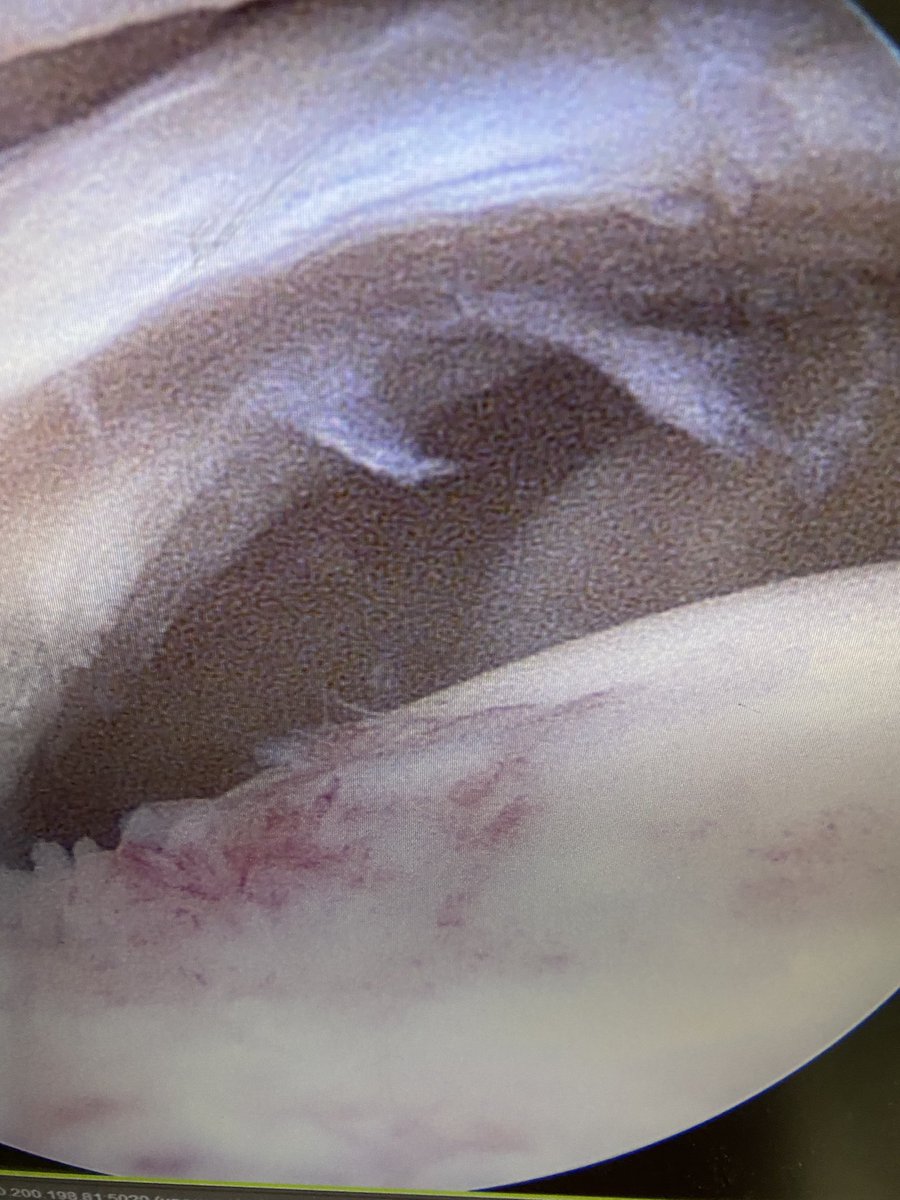

Angry pig face shoulder 🐷

Transosseous cuff repair=value based medicine